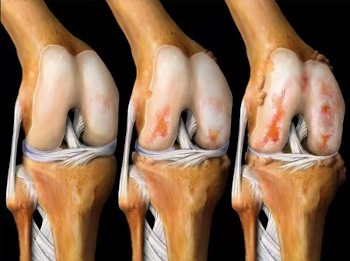

ZAPAMTITE: ARTRITIS I ARTROZA UNIŠTAVAJU HRSKAVO TKIVO ZA 3 GODINE! Nažalost, ne postoji lijek za artrozu, samo će vam operacija pomoći...

Nažalost, ljekar je bio u pravu... Već nakon 2 mjeseca bilo je strašno bolno ustajati na noge, lijekovi i masti protiv bolova su mi prestali pomagati, iako sam potrošila mnogo novca na njih, a lijekovi su mi jako štetili želucu i jetri - morala sam da odustanem od toga! Bila sam primorana da kupim invalidska kolica i da se njima krećem po stanu. Ljekar je rekao da za 3 godine artroza uništava hrskavično tkivo, ali kod mene je vjerovatno počelo mnogo ranije. Najzanimljivije je da nisam posebno ni osjetila da me bole zglobovi, a onda se nekako sve naglo pogoršalo i preko noći sam bila u kolicima, bez nade u oporavak, koliko se sjećam, suze mi se kotrljaju niz obraze, to je bio najstrašniji period mog života....